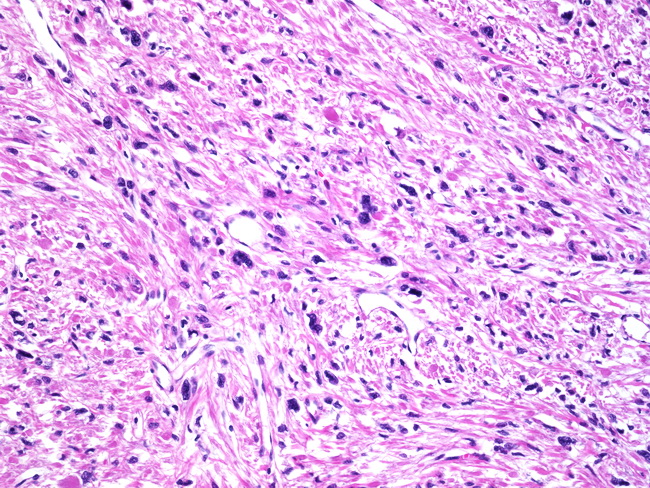

Webpathology.com: A Collection Of Surgical Pathology Images

www.webpathology.com

www.webpathology.com

uterus leiomyoma atypical bizarre webpathology pathology tumor comments